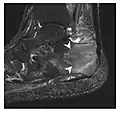

-

a -

b

Figure 14: Subcapital insufficiency fracture in a 55-year-old man with a left hip pain without a history of trauma. Anteroposterior and Lauenstein view radiographs centered on the left hip do not show an obvious fracture line, but mild acetabular osteophytosis was noted consistent with hip osteoarthritis (not shown). (a) Coronal T1-weighted MRI shows a linear low-signal band through the femoral neck corresponding to a fracture line (arrowheads). (b) Bone scintigraphy shows focal uptake (arrow) corresponding to the fracture.[1]